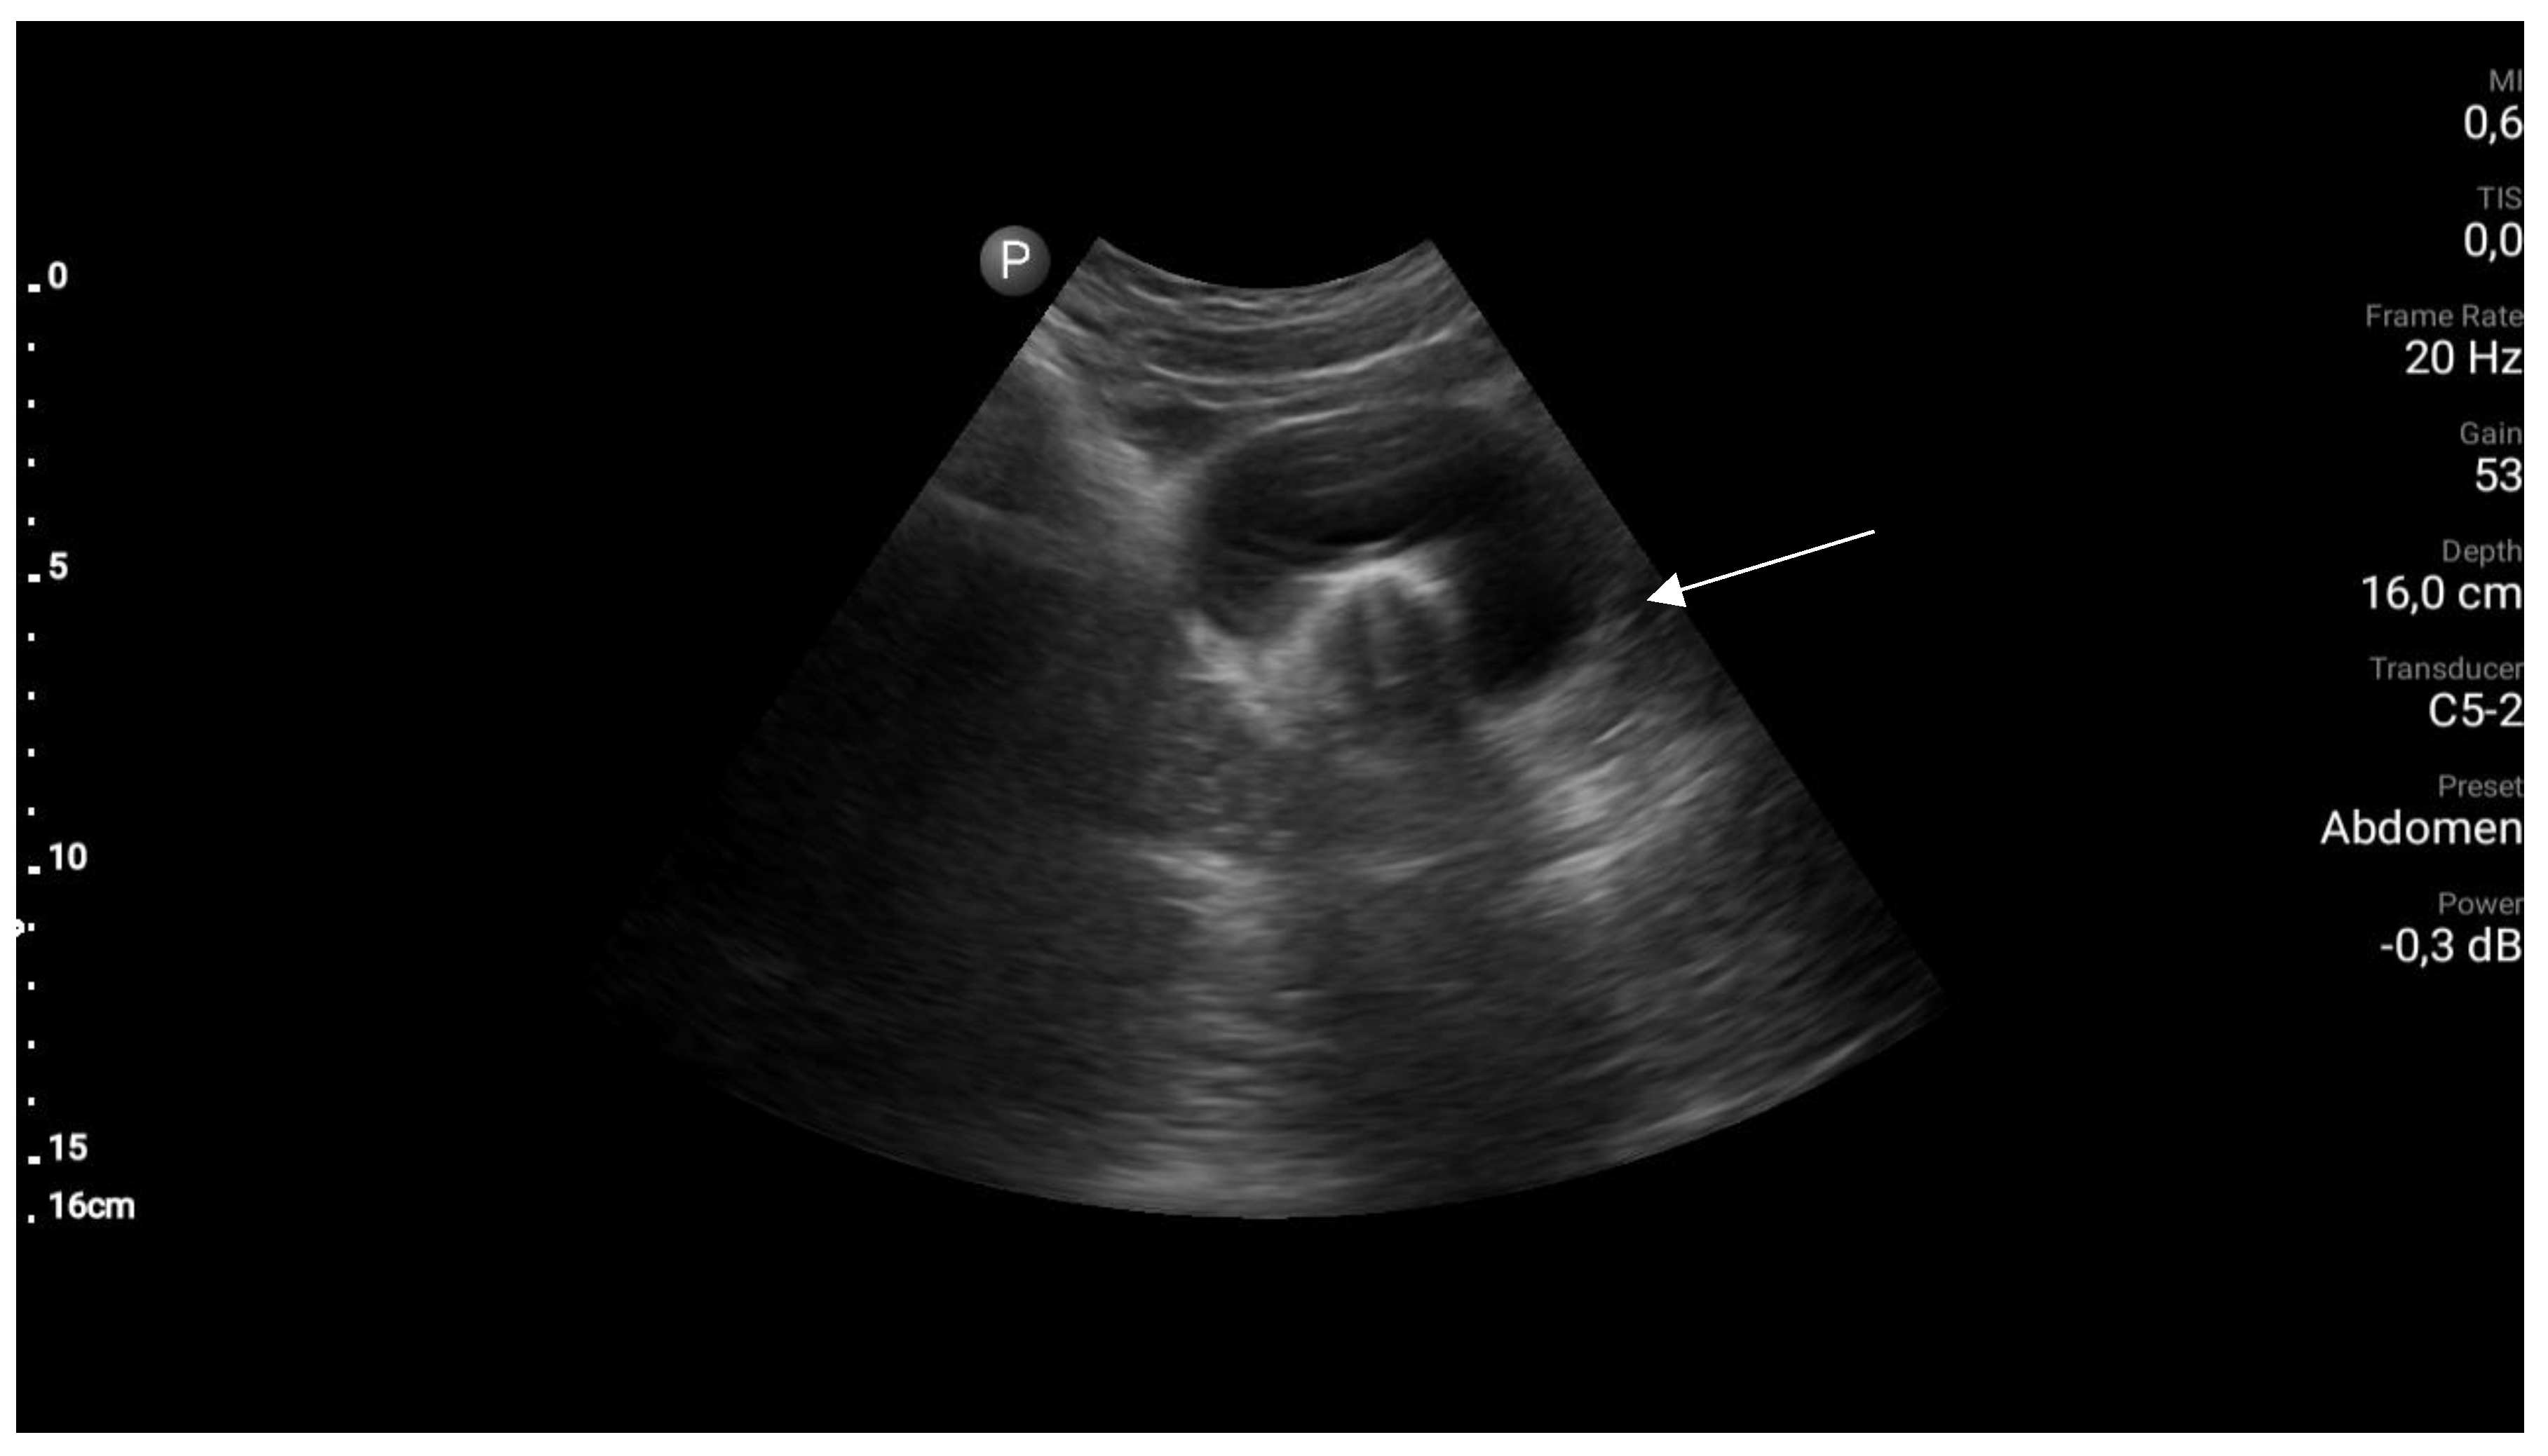

Step 1. Preoperative management Patients age (mostly occurs in young females), accurate history: time of first period, gradually increased symptoms, the appearance of symptoms during menarche, symptoms increase with each subsequent period, recurrent UTI, urinary disorders [8,9]. Perform physical examination. Next to the transabdominal US, transperineal and transrectal US can be useful in emergency situations to accurately access the place of abnormality [10]. MRI imaging should be considered as "gold standard in the diagnostic process [11]. Plan of the surgery and step by step proceeding is important while operating patients with urogenital abnormalities. As interdisciplinary collaboration of urologist and gynecologist is often necessary to treat correctly these patients. |